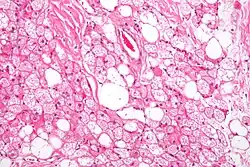

| Micrograph of a hibernoma. H&E stain. | |

The tumors histologically resemble brown fat. There are four histologic types recognized, but one is the most frequently seen (typical). There is a background of rich vascularity.

- Lobular type: Variable degrees of differentiation of uniform, round to oval cells with granular eosinophilic cells with prominent borders, alternating with coarsely multivacuolated fat cells (pale cells). There are usually small centrally placed nuclei without pleomorphism. The cells have large cytoplasmic lipid droplets interspersed throughout.[4][5]

- Myxoid variant: Loose, basophilic matrix, with thick fibrous septa, and foamy histiocytes

- Lipoma-like variant: Univacuolated lipocytes, with only isolated hibernoma cells

- Spindle cell variant: Spindle cell lipoma combined with hibernoma